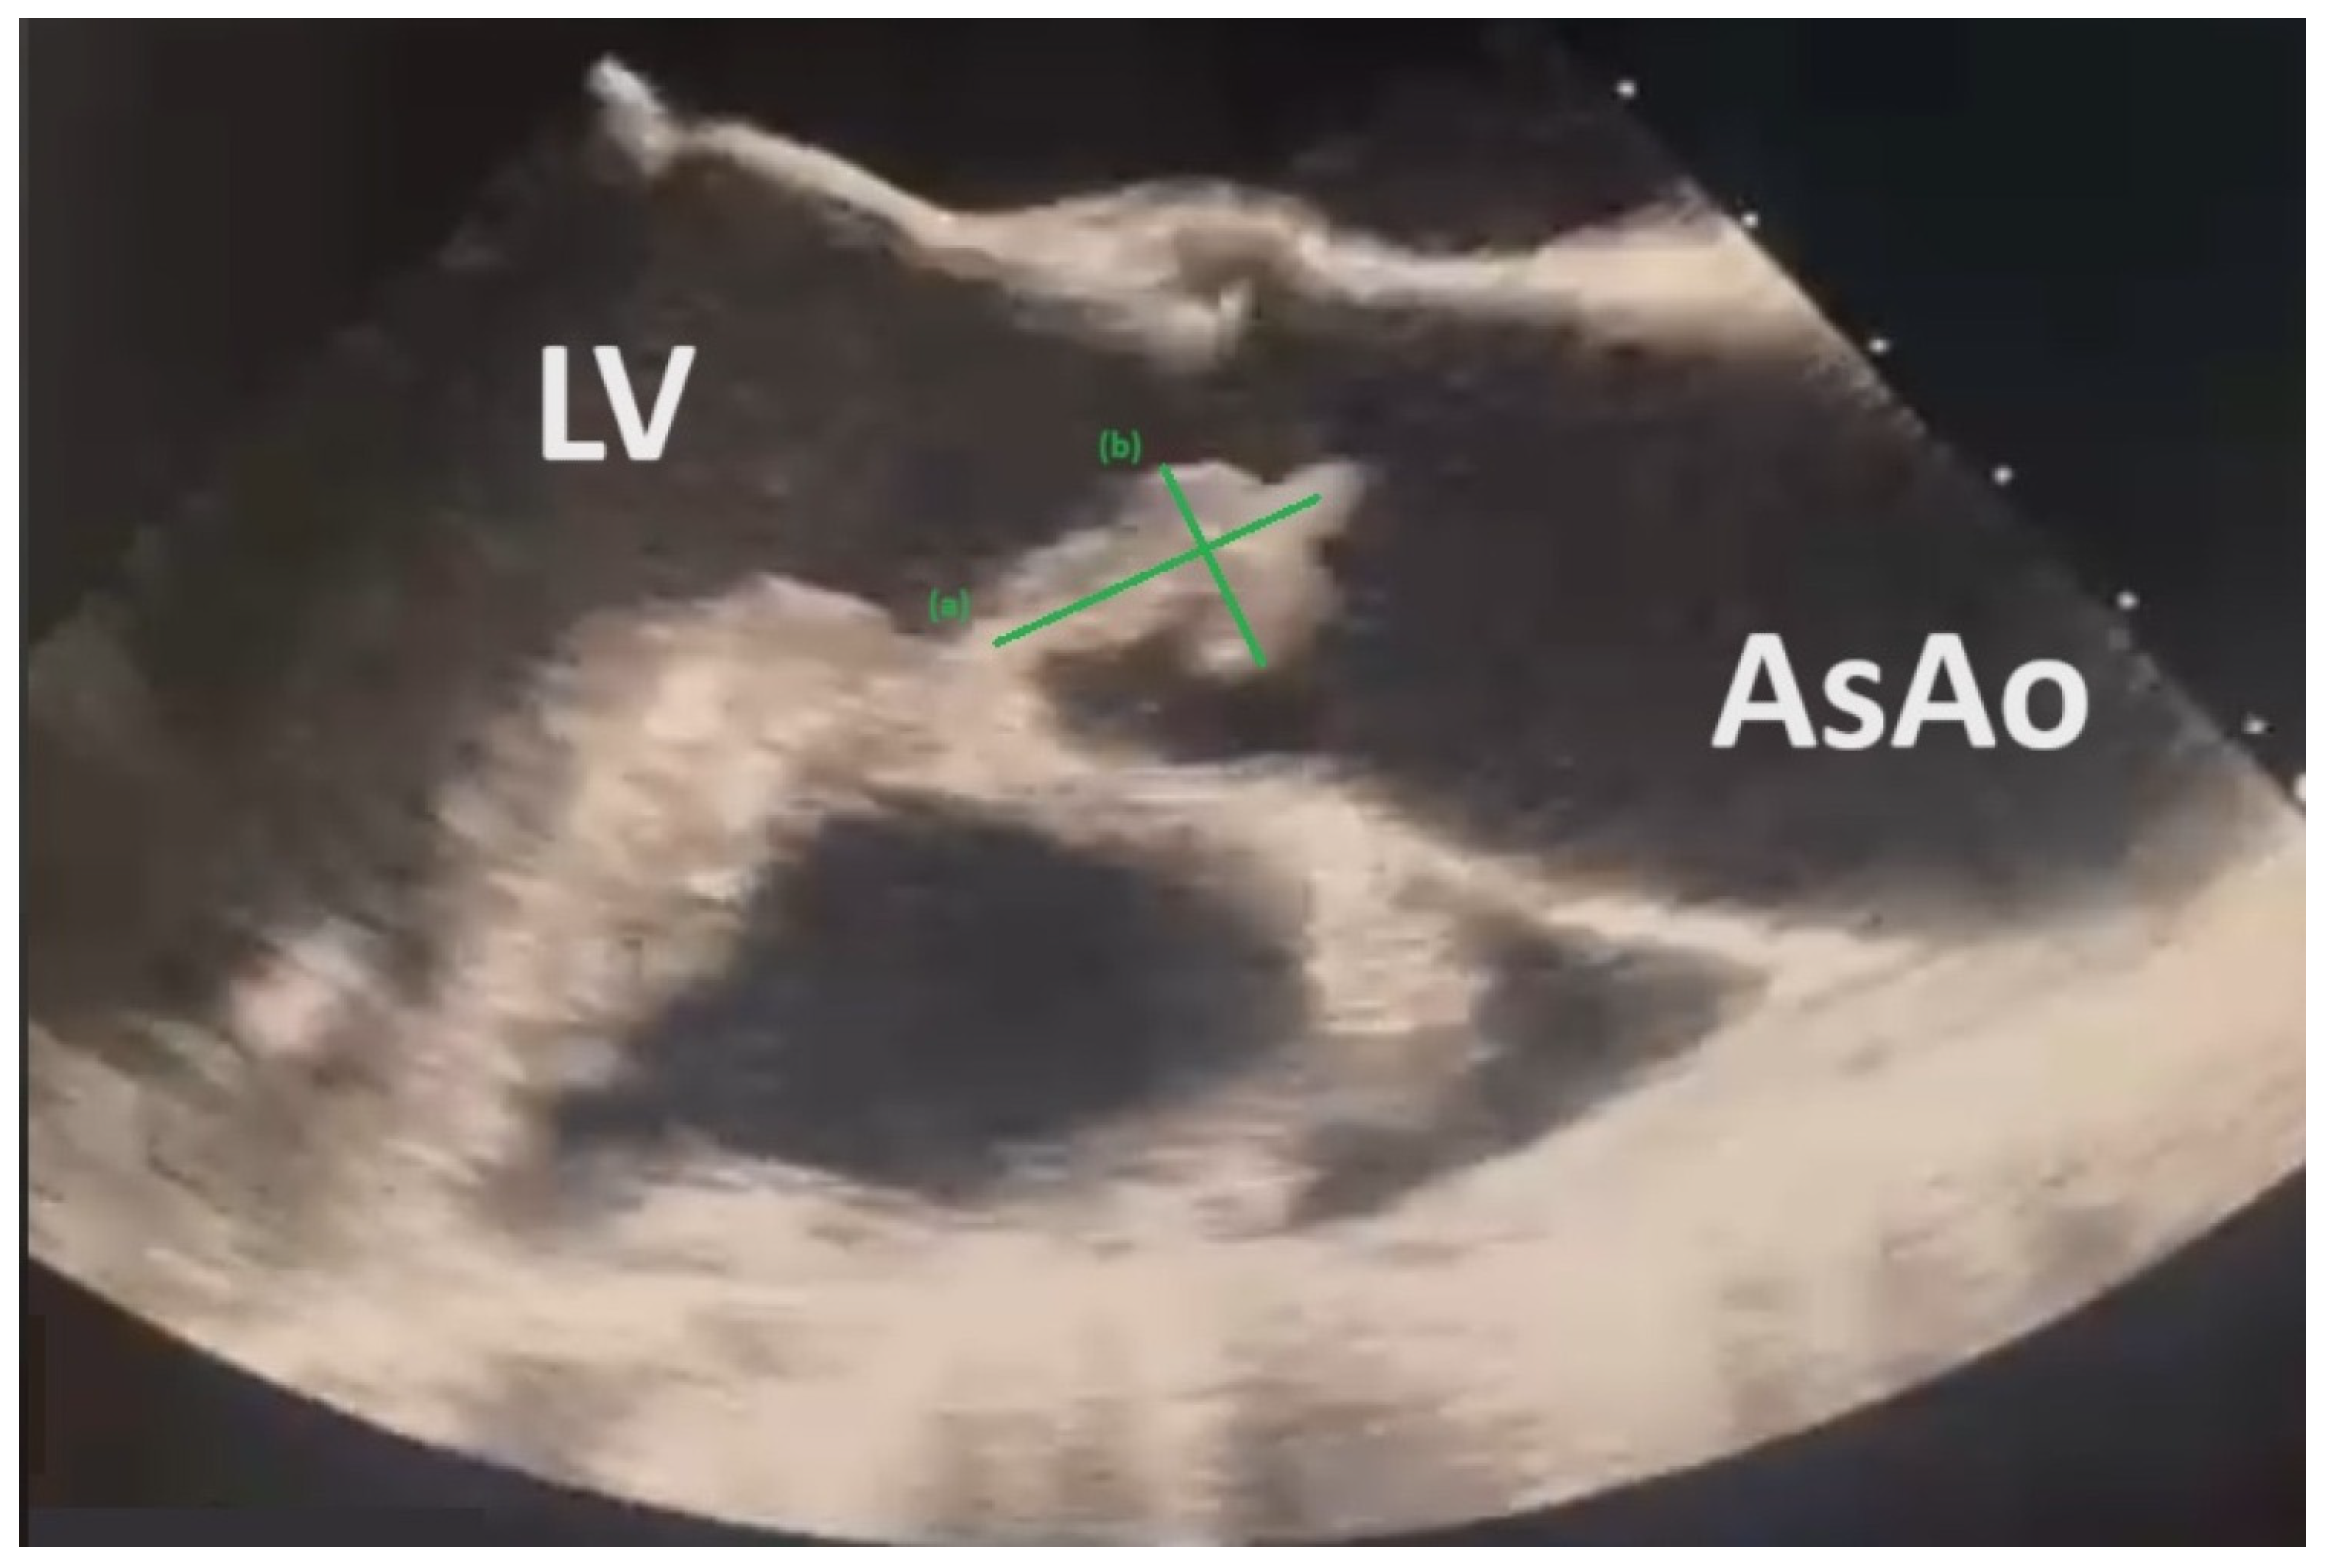

The same day, transthoracic and transesophageal echocardiograms (TTEs and TOEs) showed large-scale vegetation on the aortic valve (8.63 mm × 18.48 mm), with concomitant severe aortic insufficiency and cusp perforation consistent with the diagnosis of IE (Figure 2).

Figure 2.

TTE reveals mobile vegetation on aortic valve measuring (a) 8.63 mm and (b) 18.48 mm. Left Ventricle (LV), Ascending Aorta (AsAo).